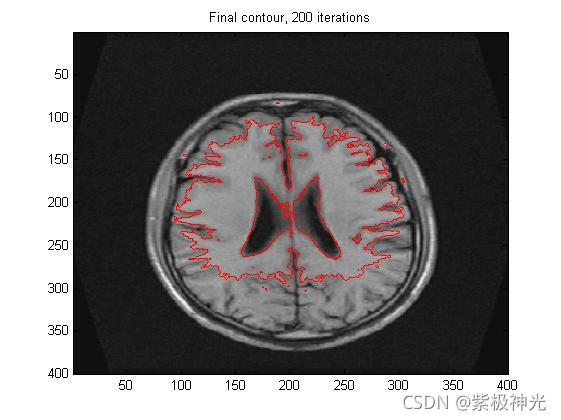

figure;

imagesc(Img, [0, 255]);colormap(gray);hold on;

contour(u,[0 0],'r');

totalIterNum=[num2str(k), ' iterations'];

title(['Final contour, ', totalIterNum]);

四、运行结果